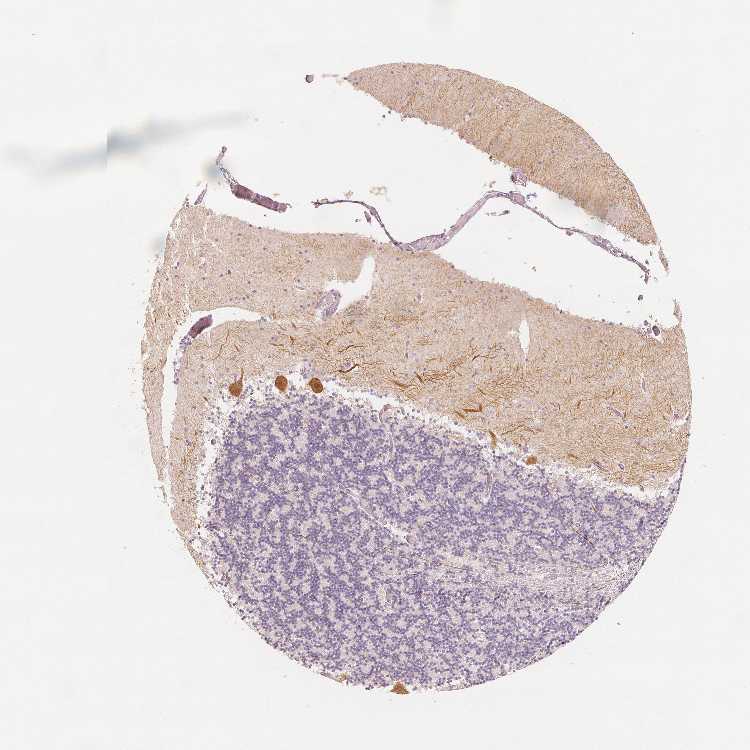

CEREBELLUM - Antibody stainingi

Antibody staining in the annotated cell types in the current human tissue is reported as not detected, low, medium, or high, based on conventional immunohistochemistry profiling in selected tissues. This score is based on the combination of the staining intensity and fraction of stained cells.

Each image is clickable and will lead to virtual microscopy that enables deeper exploration of all samples and also displays staining intensity scores, fraction scores and subcellular localization as well as patient and tissue information for each sample.

Antibody HPA023099Antibody HPA056734Antibody CAB002138

Purkinje cells High-High

Purkinje cells - cytoplasm/membrane -High-

Purkinje cells - dendrites -High-

Purkinje cells - nucleus -Not detected-

Processes in granular layer -High-

Processes in molecular layer -High-

Processes in white matter -High-